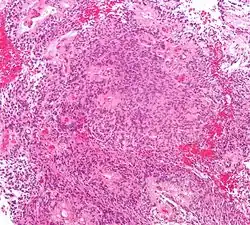

| Micrograph of an ependymoma. H&E stain. | |

Ependymomas are composed of cells with regular, round to oval nuclei. There is a variably dense fibrillary background. Tumor cells may form gland-like round or elongated structures that resemble the embryologic ependymal canal, with long, delicate processes extending into the lumen; more frequently present are perivascular pseudorosettes in which tumor cells are arranged around vessels with an intervening zone consisting of thin ependymal processes directed toward the wall of the vessel.[5]